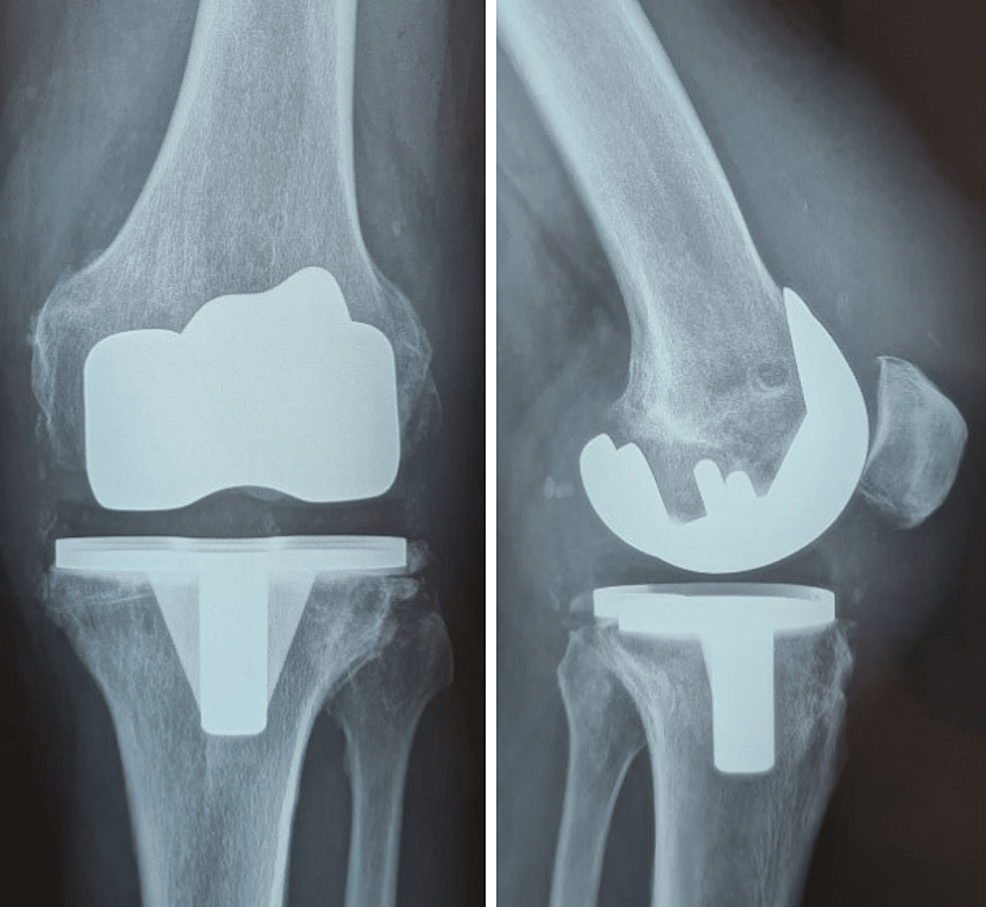

What is Total Knee Replacement(TKR)? Symptoms, Causes, Diagnosis & Physiotherapy Treatment of Is Heat Good For Tkr Although ice gets most of the attention (and should), heat too plays a role to help joints, muscles, and ligaments as they recover and regain strength through physical therapy. However, the introduction of this method into your plan at the right stage of recovery will speed it up. — if you've had total knee replacement (tkr) surgery, you might. Is Heat Good For Tkr.